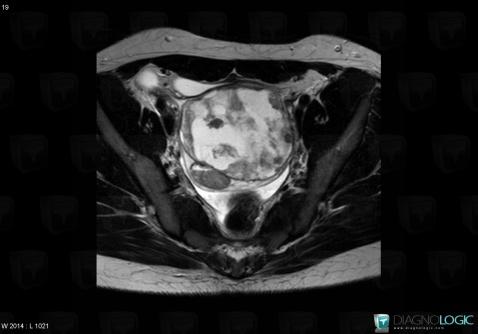

Tumeur-sac vitellin, Annexe / Ovaire - trompe, Pelvis / Périnée, IRM

Voici les informations spécifiques à l'image clé ci dessus:

- Diagnostic Tumeur du sac vitellin, Localisation(s) Pelvis / Périnée, comportant les gammes Masse pelvienne complexeAnnexe / Ovaire - trompe, comportant les gammes Masse annexielle complexe